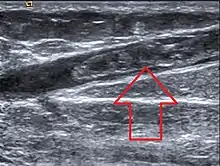

Paradoxically, progestogens do promote the growth of uterine fibroids, and a pelvic ultrasound can be performed before beginning HRT to make sure there are no underlying uterine or endometrial lesions.[53]